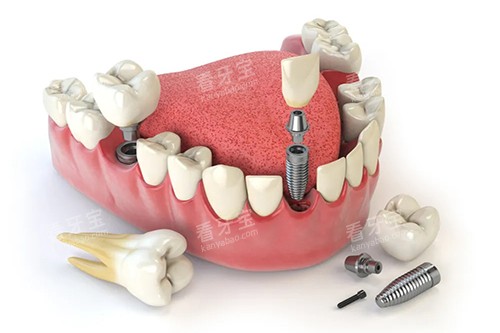

上海鼎植口腔在口腔种植领域拥有多项专有技术,这是其强大实力的体现。

其中,穿颧穿翼种植技术是鼎植口腔的一大特色。

对于一些牙槽骨条件较差、传统种植方式难以实施的患者来说,穿颧穿翼种植技术为他们带来了新的希望。

该技术通过将种植体植入颧骨或翼板等部位,无需进行骨增量手术,大大缩短了治疗周期,减少了患者的痛苦。

鼎植口腔的医生团队在穿颧穿翼种植技术方面有着丰富的临床经验,已经成功为众多患者解决了牙齿缺失问题,让他们重新拥有了健康的牙齿和自信的笑容。

此外,鼎植口腔还引进了可靠的智能化口腔诊疗技术。

智能化口腔技术可以实现口腔数据的比较准采集和分析,医生可以根据患者的口腔模型和数据进行个性化的治疗方案设计。

在种植手术中,通过智能化导板的引导,种植体的植入更加比较准、可靠,大大提高了手术的可行性和治疗结果。